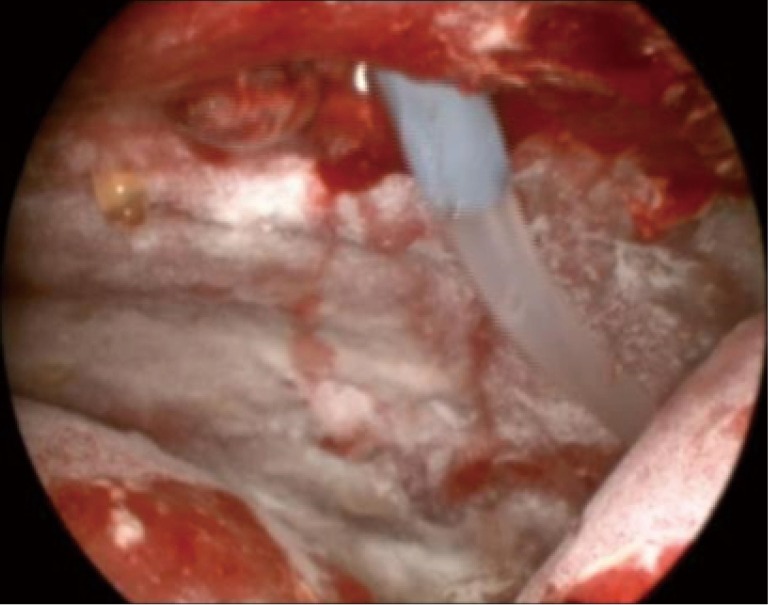

All procedures were performed by an interventional pulmonologist with experience in thoracoscopy/TPC placement. A single 8 or 10 mm port was utilized. Pleural fluid was evacuated and the space visually inspected. Pleural biopsies were performed at the discretion of the interventional pulmonologist. TPC (PleurX; Care Fusion; McGaw Park, Illinois or Rocket; Rocket Medical; Hingham, MA) placement was then performed under direct visualization followed by insufflation of 4 to 5 grams of commercially available sterile talc (Figure 1). Depending on physician preference, a 19–24 French chest tube was placed through the site of the port to ensure continued drainage of the pleural space. The chest tube was placed to −20 cm H2O suction. The TPC was placed to −20 cm H2O suction rather than subsequent chest tube placement in one patient. Per protocol, an overnight admission with continuous chest tube drainage and pain management was required. Patients were then discharged with the TPC in place and instructions for daily home drainage. Once catheter output was deemed to be minimal, which was consistently less than 150 mL per day at home, patients contacted the physician to arrange for TPC removal. Pleural ultrasound to evaluate for residual effusion and/or radiographic imaging prior to TPC removal was at the discretion of the physician.

Figure 1.

Intra-procedural image of the pleural space following insufflation of talc and placement of the TPC. TPC, tunneled pleural catheter.